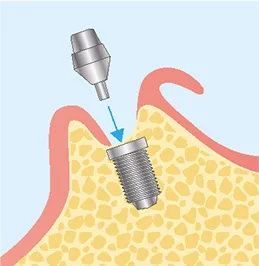

FLOW02

二次オペ

(アバットメントの装着)-

STEP1

麻酔

STEP2

歯ぐきの切開

STEP3

アバットメント埋入

STEP4

縫合